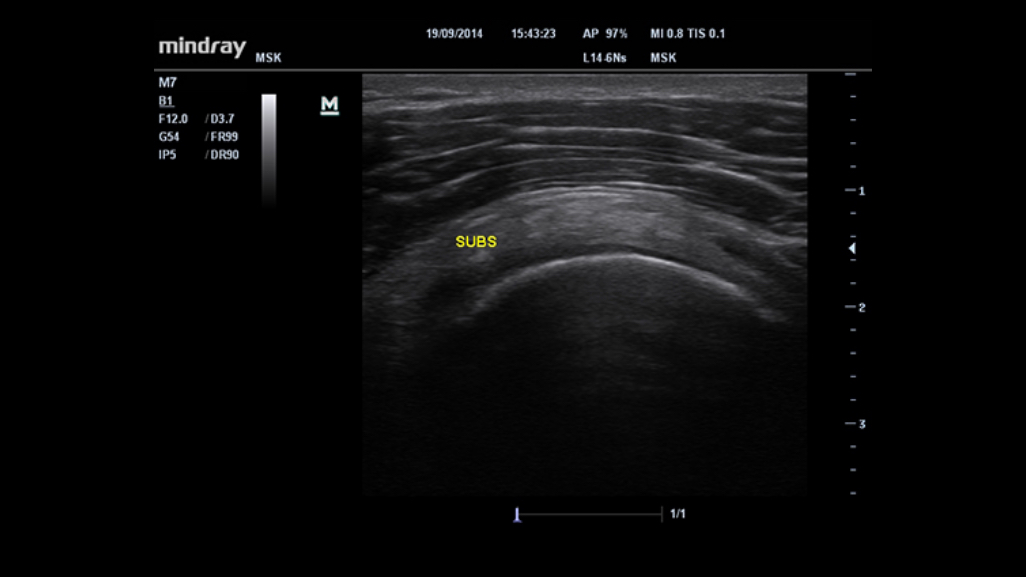

M7 Premium

M7 Premium

With its ergonomic mobile trolley same with performance and features comparable to that of conventional cart-based systems, the M7 Premium provides you mobility with power and improves your productivity. To sum it up, the M7 Premium delivers you the power and productivity of a full-sized system in a hand-carried size.